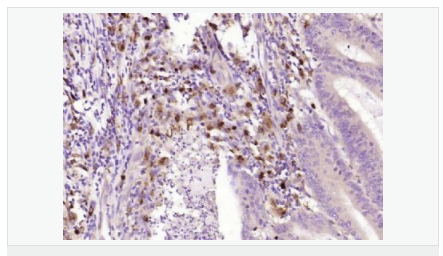

產品應用WB=1:500-2000 ELISA=1:5000-10000 IHC-P=1:100-500 IHC-F=1:100-500 ICC=1:100-500 IF=1:100-500 (石蠟切片需做抗原修復)

產品介紹This gene encodes an aldo-keto reductase that catalyzes the NADPH-dependent reduction of pteridine derivatives and is important in the biosynthesis of tetrahydrobiopterin (BH4). Mutations in this gene result in DOPA-responsive dystonia due to sepiaterin reductase deficiency. A pseudogene has been identified on chromosome 1. [provided by RefSeq, Jul 2008]

Catalyzes the final one or two reductions in tetra-hydrobiopterin biosynthesis to form 5,6,7,8-tetrahydrobiopterin.